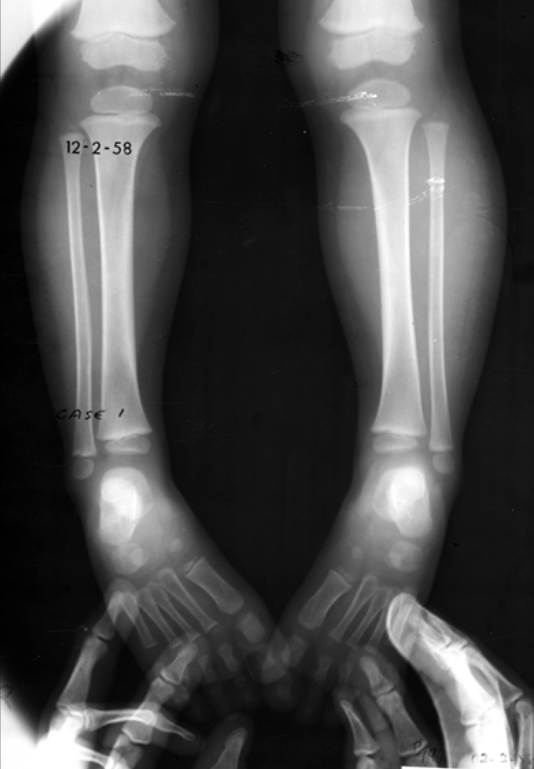

6

Q

3-year-old male presents with leg pain and swelling. He is radiographed several days into his symptoms.

What radiographic infectious terms are present?

A

• Sequestrum

• Involucrum

• Cloaca

osteomyelitis

permeative lytic destruction (aggressive)